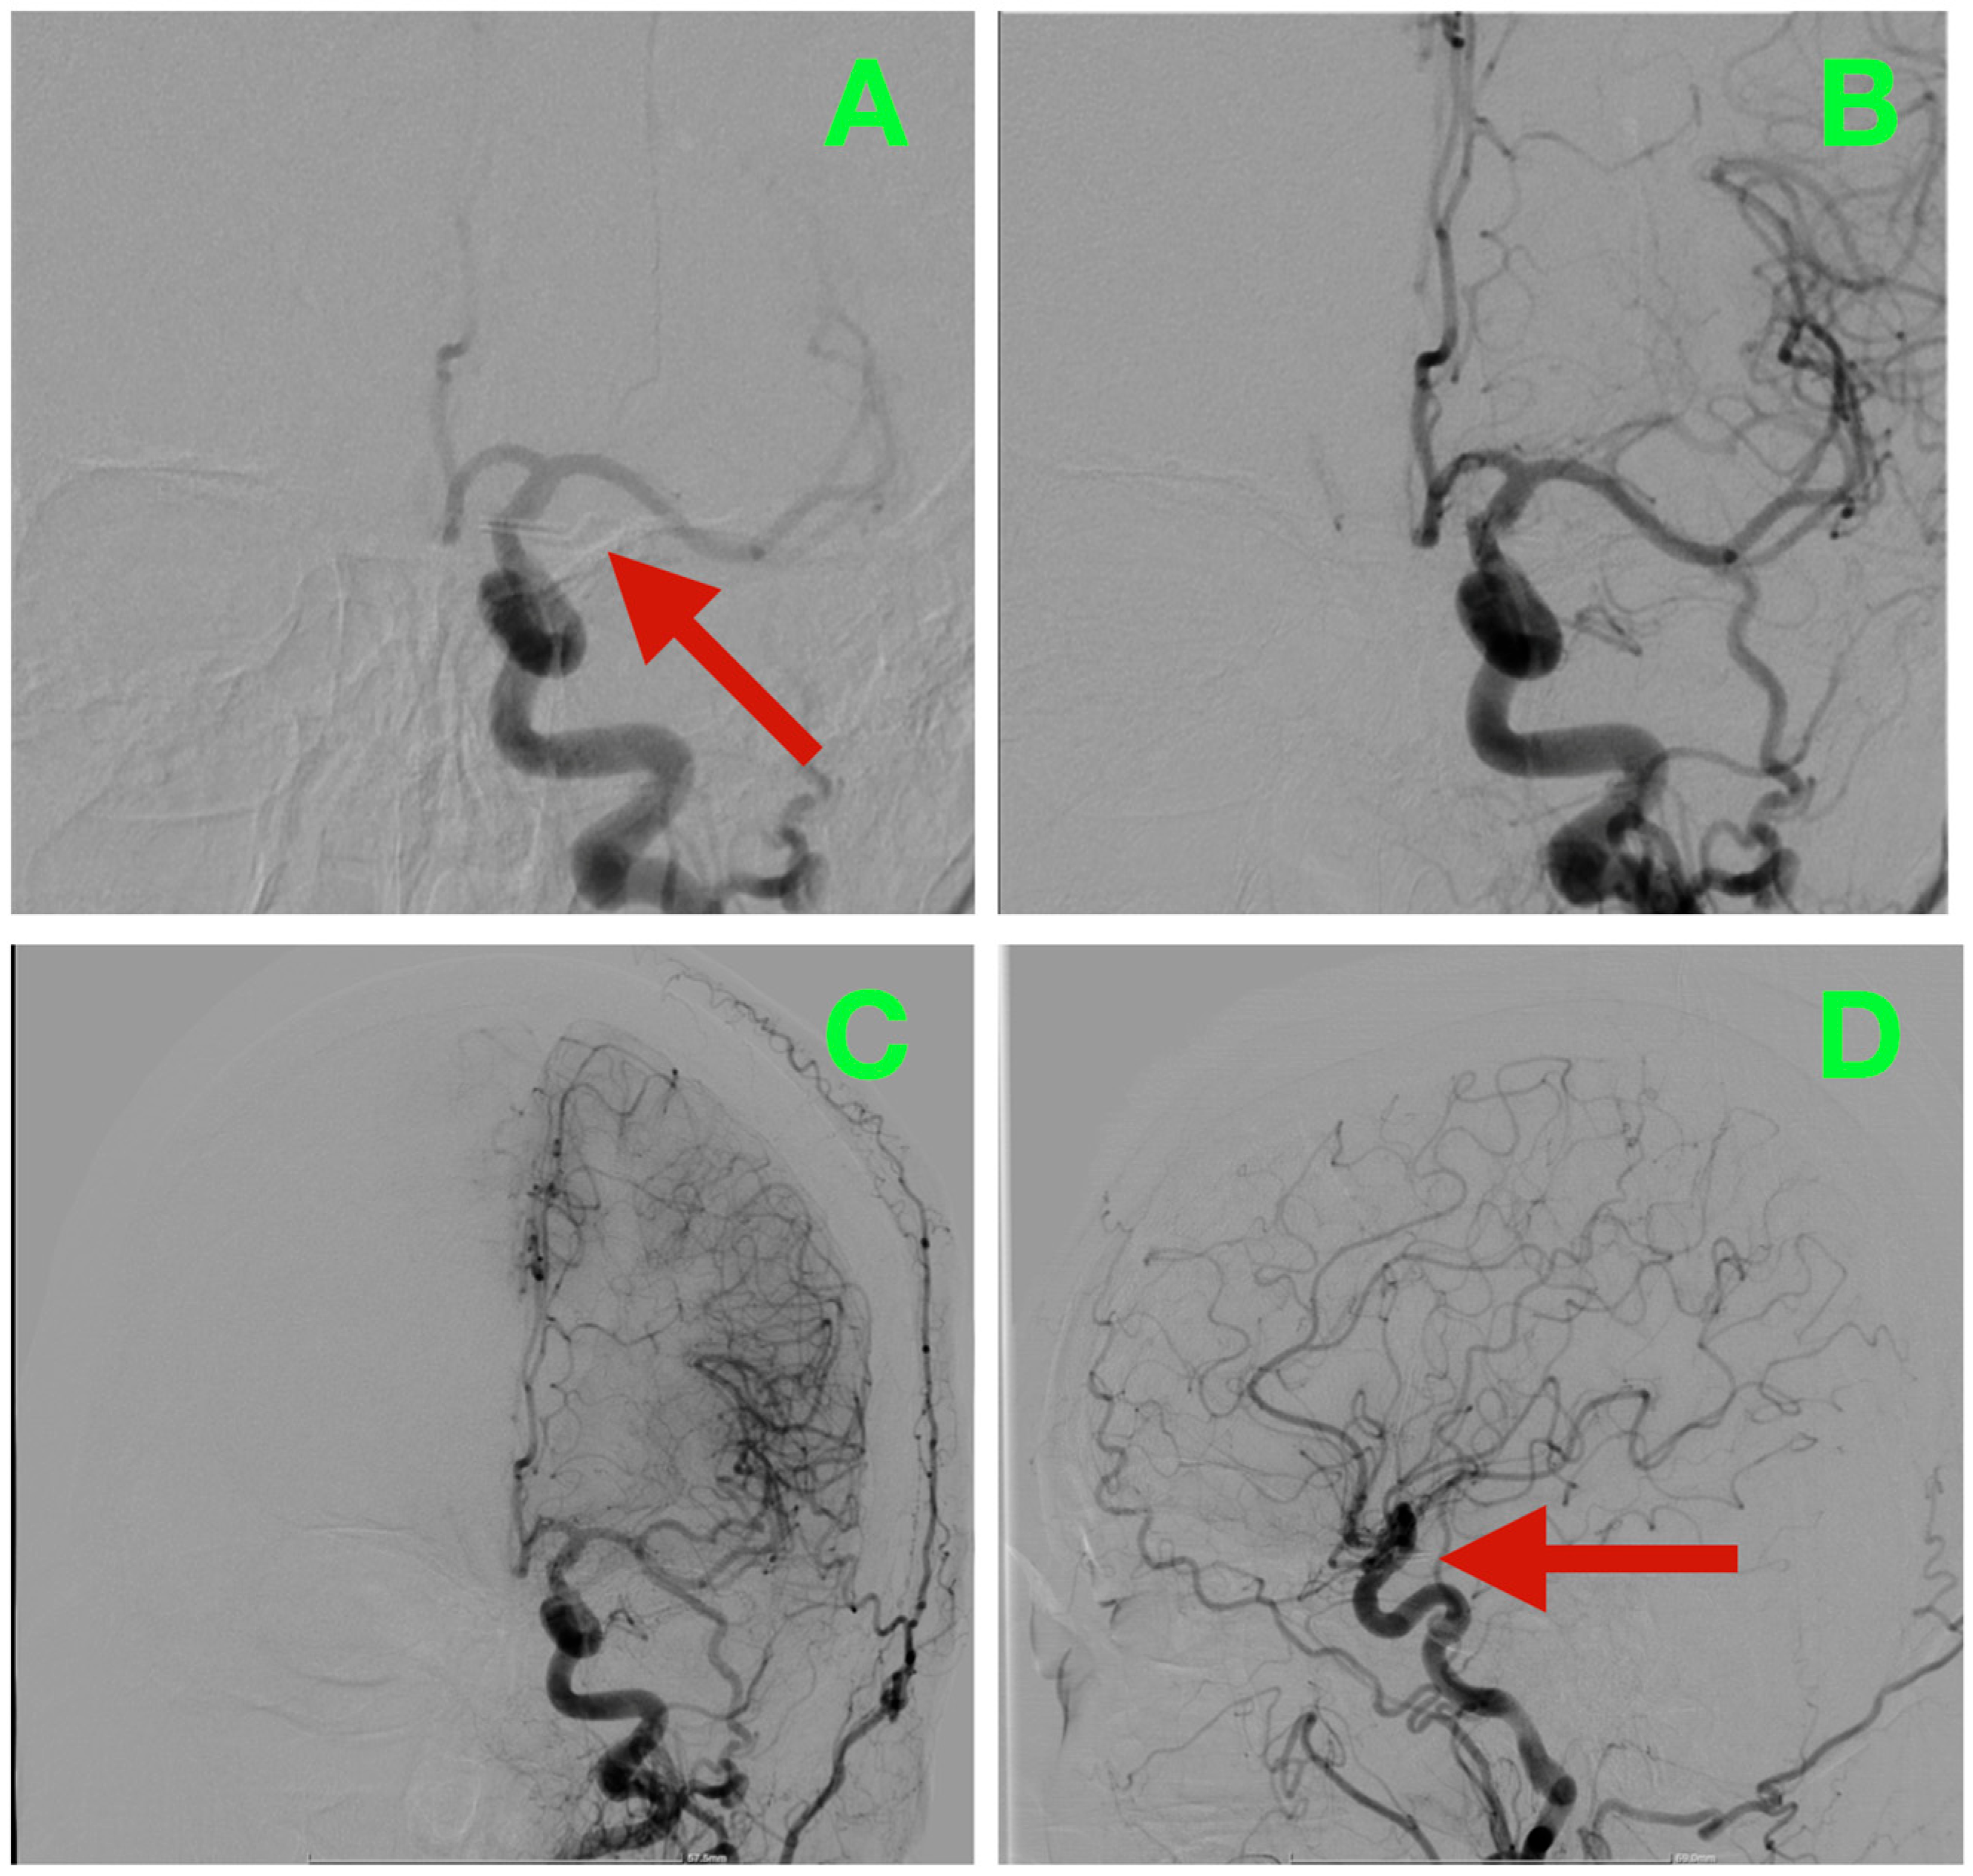

2.6. Preoperative Angiographic Findings